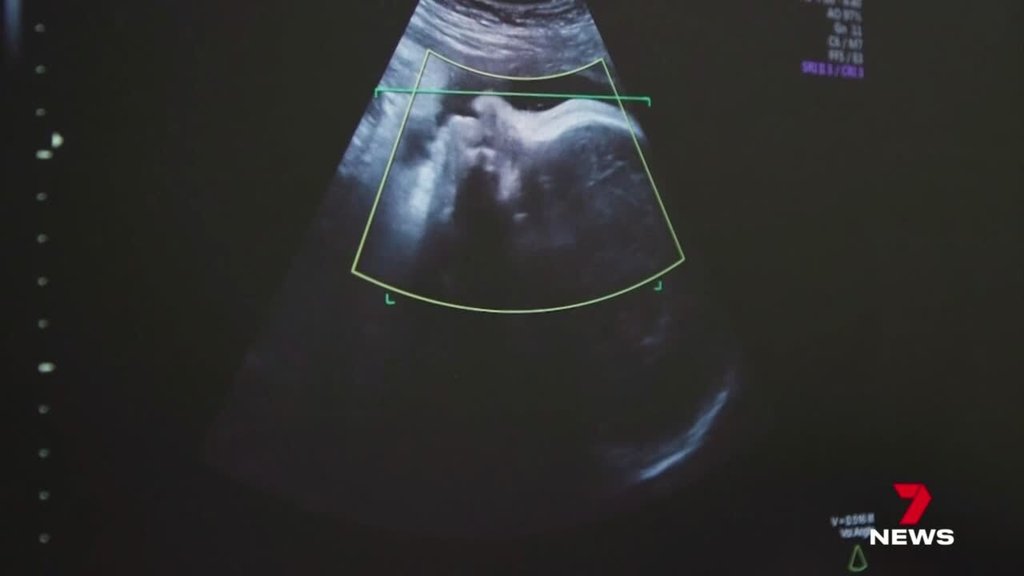

Millions of workers could be set to get an extra 12 days off in paid reproductive leave to cover treatments such as severe period pain, menopause, gender transition, IVF, and vasectomies if a new union proposal succeeds.

The leave would cover a range of reproductive and fertility treatments and procedures including hormone therapy, miscarriage, screenings for breast and prostate cancer, and polycystic ovary syndrome.